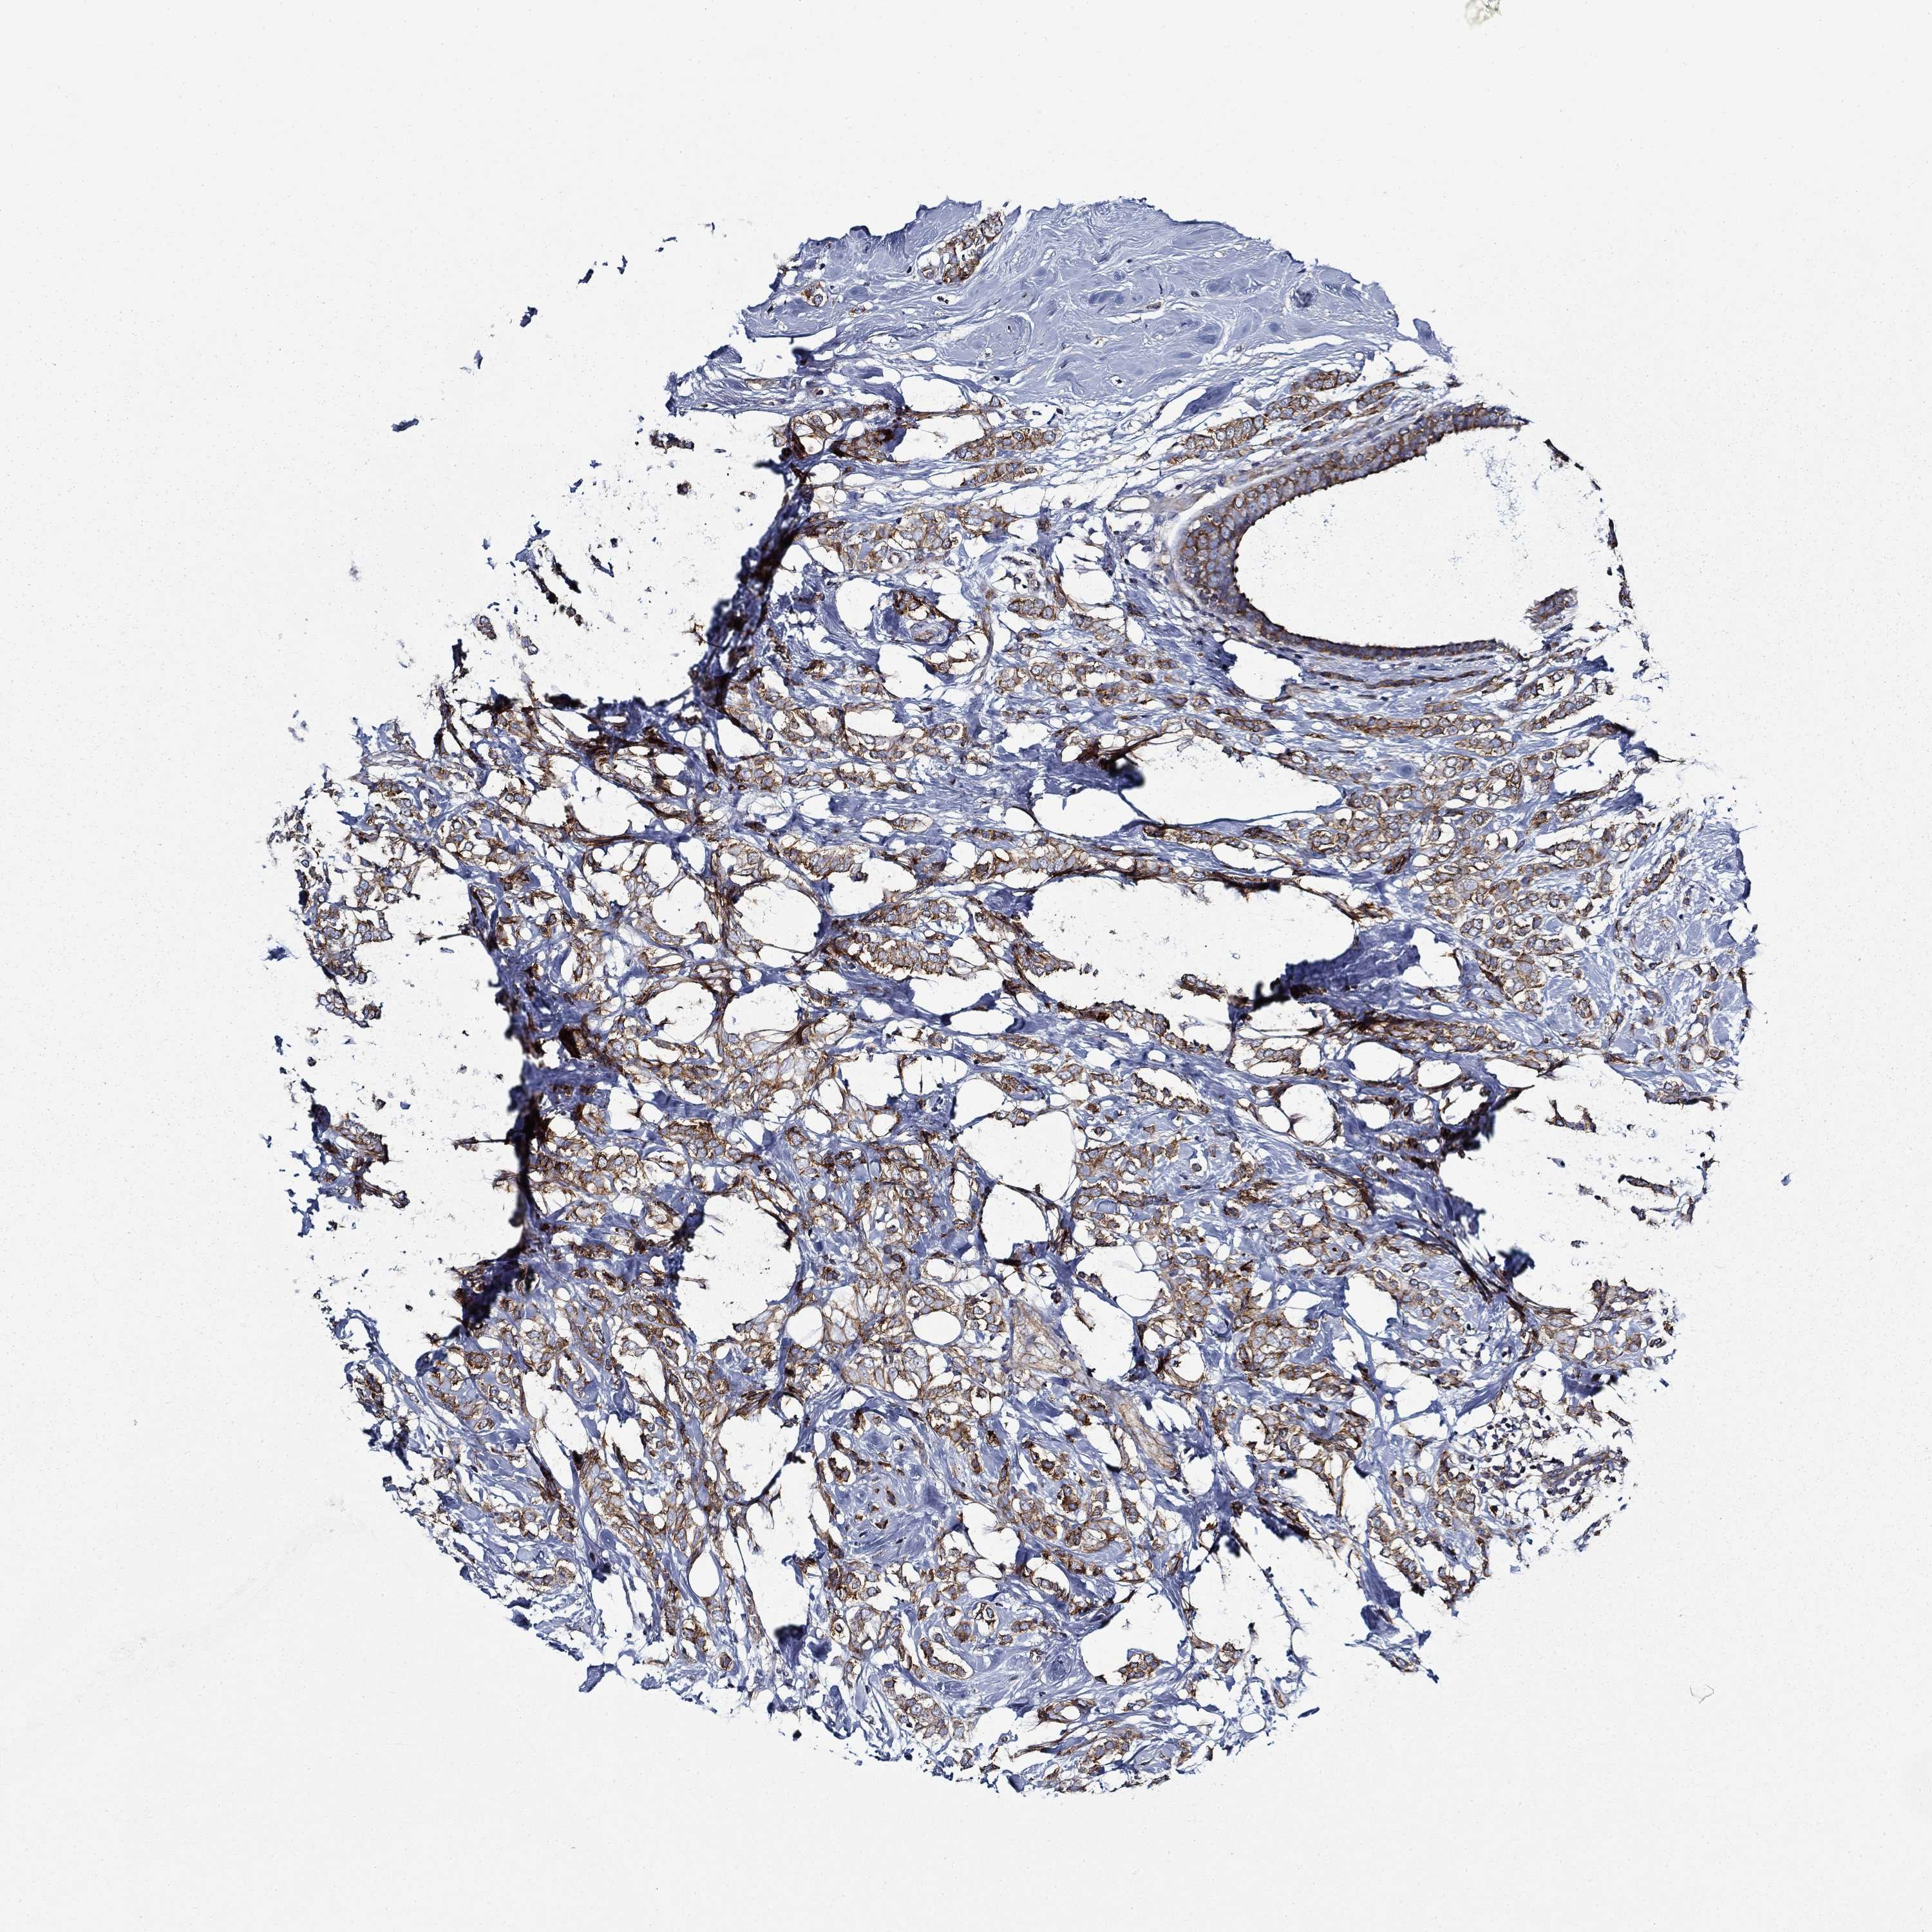

BRCA TCGA BRCA VALIDATION PROTEIN EXPRESSION

ANTIBODIES

AND

VALIDATION